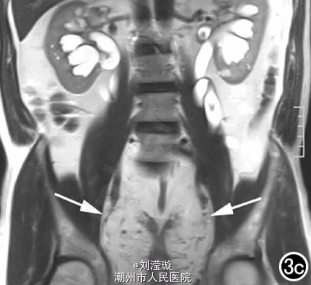

腹部B超示双肾增大,双肾慢性肾病声像;双肾中度积液伴双输尿管上段扩张。 IVPshi双侧输尿管中或下段梗阻。 膀胱造影:经尿道置管后,注射对比剂充盈膀胱,膀胱下半部先充盈,继续灌注对比剂后见膀胱完全显影,膀胱形态异常,呈“倒葫芦状”(图1)。 CT增强扫描行延迟期 MPR重组,见双侧肾盂、肾盏扩张积液;双侧输尿管纡曲、扩张,下端呈鸟嘴样变窄;膀胱变形、体积减小(图2); MRI平扫示双侧肾盂、肾盏扩张积液,双侧输尿管扩张并下端鸟嘴样变窄,盆腔内多量脂肪沉积,分布于膀胱、直肠周围,T1WI、T2WI呈明显高信号,T2WI抑脂像呈稍高信号,膀胱受压变形、体积减小(图3a~c); MRU示双侧肾盂肾盏扩张、积液,双侧输尿管显著纡曲、扩张,下端鸟嘴样变窄,管壁光整,膀胱变形、体积较小、位置抬高(图3d)。